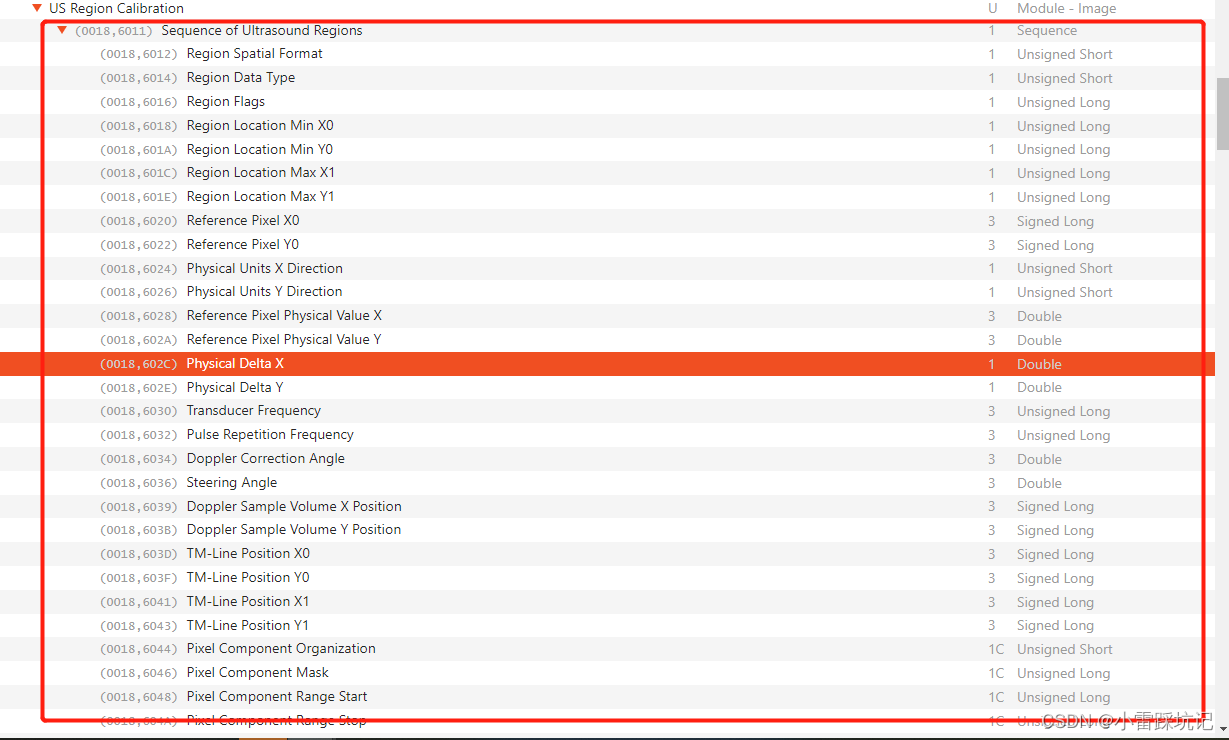

查了很多资料,发现针对us这种类型,dicom会有特殊的sequence记录下其物理的像素.

其中

PhysicalDeltaX ,PhysicalDeltaY 就是要我们要找寻的字段